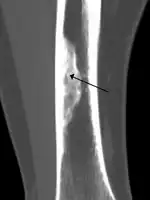

| X-ray of nonossifying fibroma of distal tibia. | |

Diagnosis is by X-ray or MRI, usually when investigating a person for something else.[2] Medical imaging typically shows a well defined radiolucent lesion, with a distinct multilocular appearance, sometimes looking like bubbles.[2] It is usually around 1–2 cm in size, but be as large as 7 cm.[3] They consist of foci consist of collagen rich connective tissue, fibroblasts, histiocytes and osteoclasts.[2] Usually no treatment is required.[1] Surgical curettage and bone grafting may be required if it is large.[3]

It is usually diagnosed by x-ray or MRI, when investigating another problem.[1] The tumor presents as a well defined radiolucent lesion, with a distinct multilocular appearance, sometimes looking like a "soap bubble".[5] If small and no symptoms, then biopsy is not needed.[1]